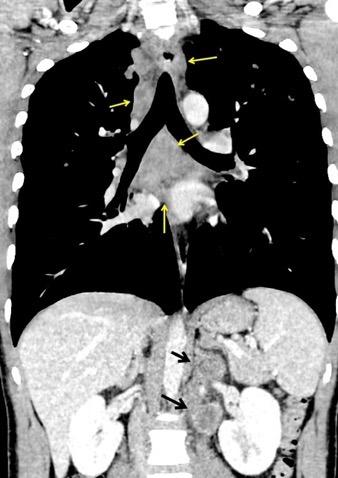

Nódulos pulmonares múltiples. (flechas verdes). Masas paratraqueales. (flechas amarillas). Dudoso ensanchamiento retrocrural (flechas negras). sigue….

Ttawfik A et al. Trans-diaphragmatic Pathologies: Anatomical Background and Spread of Disease on cross-sectional Imaging. Current Problems in Diagnostic Radiology. 2021.

T. mixto de células germinales del testículo

izquierdo Metástasis pulmonares. (flechas verdes). Ganglios paratraqueales. (flechas amarillas). Ganglios retroperitoneales (flechas negras)

Tawfik A et al. Trans-diaphragmatic Pathologies: Anatomical Background and Spread of Disease on cross-sectional Imaging. Current Problems in Diagnostic Radiology. 2021.